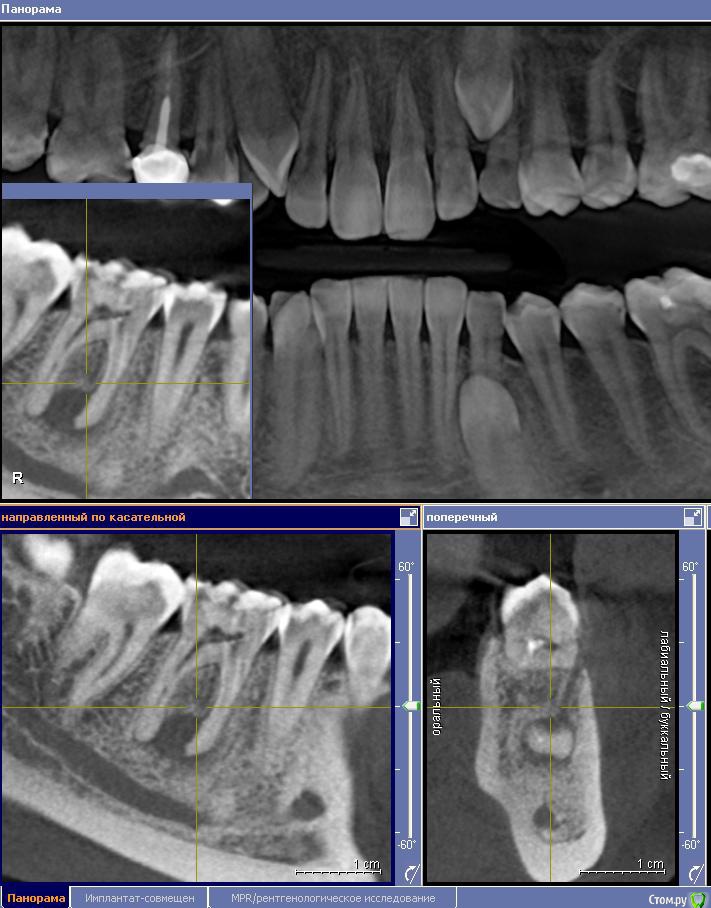

Ксения_ Опубликовано 27 августа, 2015 Поделиться Опубликовано 27 августа, 2015 (изменено) Здравствуйте Уважаемые Доктора! КТ сделано 4 мес назад. После этого пролечен кариес 14, 16, 37, 35. Пролечен пульпит 25, 36.Осталось пролечить пульпит в 15, 26, 47. Удалить все восьмерки.Далее ортодонтия. Стоит вопрос об удалении 46. Зуб ранее был пролечен другим врачом некачественно (+ пропущен канал).Мой лечащий доктор, после консультаций с коллегами, предлагает удаление, т.к. с его слов прогноз у этого зуба неблагоприятный (считает, что через пару лет процесс повторится) и смысла в столь дорогом лечении нет. Мне, конечно, хотелось бы по возможности зуб сохранить.Как вы считаете какой прогноз у этого зуба? P.S. Зуб не беспокоит. Точнее ни один зуб у меня вообще ни разу в жизни не болел (несмотря на такое количество пульпитов, которые для меня были неожиданностью. Врачу своему доверяю.). Несколько докторов которые меня смотрели считают, что у меня высокий болевой порог. Изменено 27 августа, 2015 пользователем Ксения_ Ссылка на комментарий

M@estro Опубликовано 27 августа, 2015 Поделиться Опубликовано 27 августа, 2015 (изменено) Судя по рентгену - прогноз благоприятный. Зуб сохранен,это главное. "процесс повторится" - на это при современном подходе выделяют не более 5 % .Если бы у меня 95 % вероятности в казино было - я бы дом поставил , не то что зуб полечил ) Ключевое при перелечивании - соблюдение современного протокола лечения. P.s. После лечения уже больше двух лет прошло,недавно был на осмотре - процесс все никак не повторится )) Изменено 27 августа, 2015 пользователем M@estro 3 Ссылка на комментарий